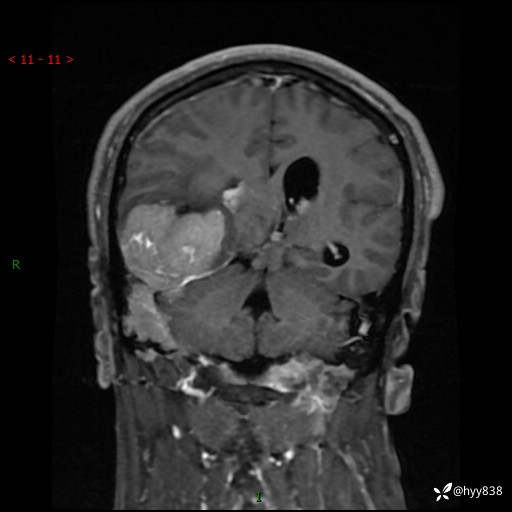

患者性别:男

患者年龄:56岁

简要病史:外院CT提示脑膜瘤,为进一步诊治来我院

临床诊断:颅脑占位

颅脑MRI平扫+增强